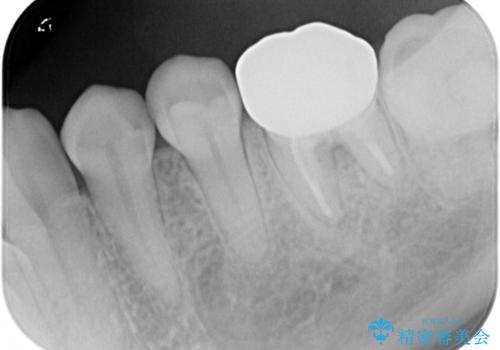

- 他院で自費根管治療、矯正治療、セラミック治療をする予定でしたが、根管治療終了後から忙しく通わなくなり放置していました。

海外転勤が決まったため、それまでに治療をしてほしいとご来院されました。(矯正治療はせずにセラミック治療のみ)

海外転勤が決まり、急いでセラミック治療をしてほしいとご来院された患者様です。

根管治療に症状がなく、上の歯に関しては土台もそのまま使用可能であったため、下の歯の土台、上下の歯のセラミック治療を行いました。